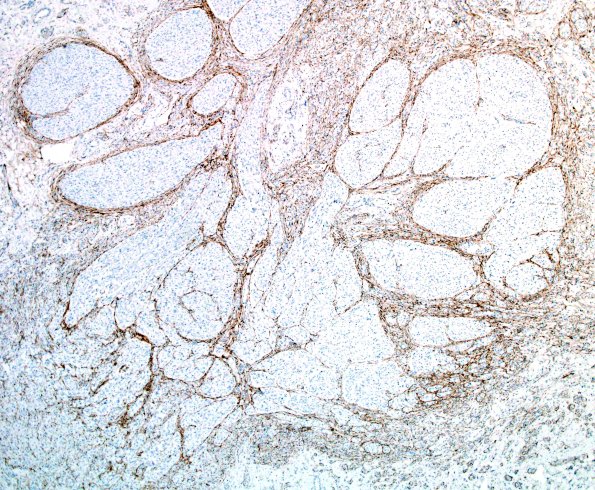

Washington University Experience | PERIPHERAL NEUROPATHY | 19 TRAUMATIC INJURIES | 4D1 Neuroma (Case 4) EMA 4X

4D1,2 This neuroma has large fascicles of the residual nerve and halos of mini-fascicles surrounding them. (EMA IHC)